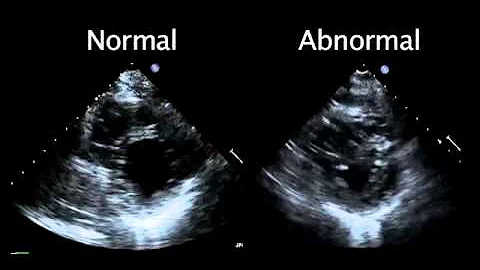

Any Remedy For Rwma (regional Wall Motion Abnormality)?

Regional wall motion abnormality or